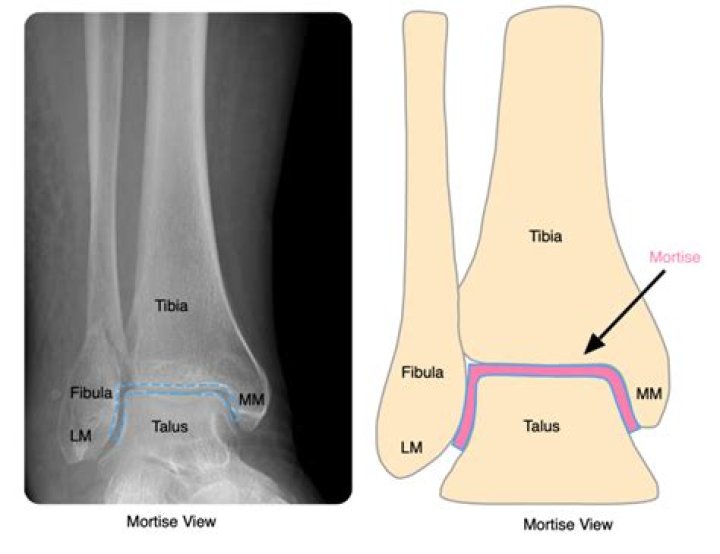

The ankle joint is a hinged synovial joint that is formed by the articulation of the talus, tibia, and fibula bones. Together, the three borders (listed